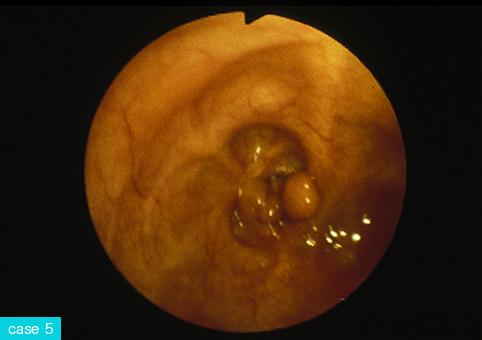

Seven cases of inflammatory polyposis recognized in intestinal tuberculosis.

Tumor-like lesions/Inflammatory polyposis

Location

Large intestine(Colon)/Ascending colon

Technique, Method

Endoscopy

Size